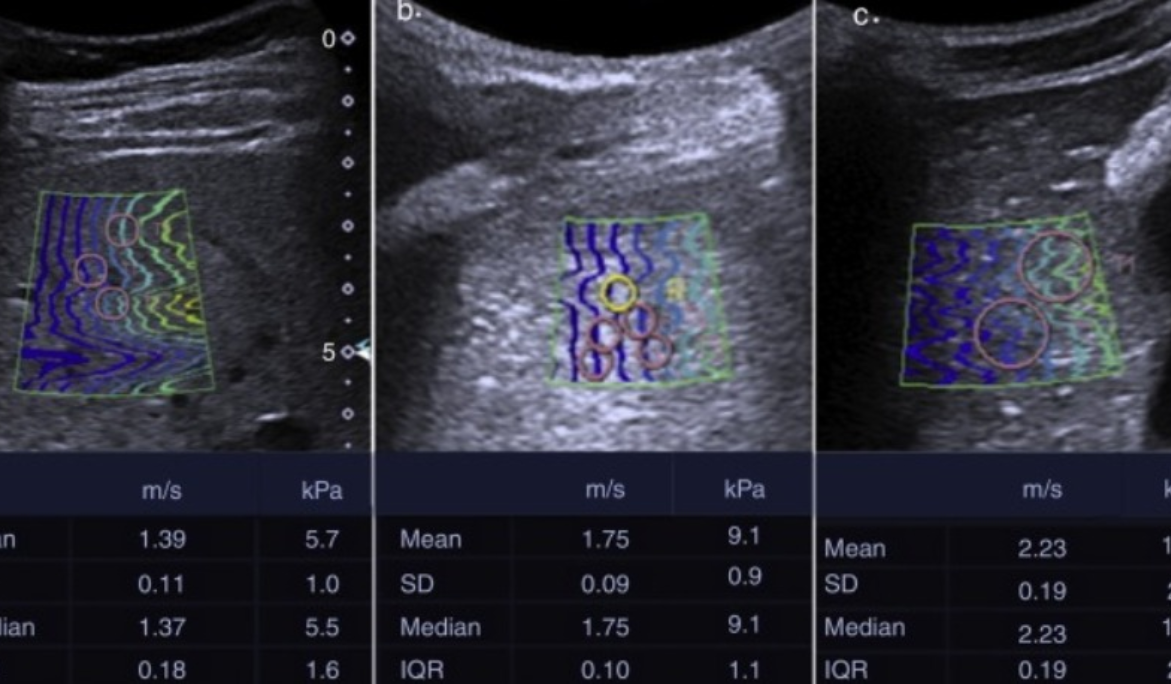

Las elastografía utiliza vibraciones de baja frecuencia durante un ultrasonido o una RMN para medir la rigidez (o elasticidad) de órganos internos. Es particularmente útil para detectar la presencia y la gravedad de enfermedades del hígado. Con un procedimiento de elastografía es posible detectar el grado de fibrosis y cirrosis del hígado.. En el proceso, la cabeza sónica envía una onda de baja frecuencia dentro del tejido hepático cuya velocidad de propagación se mide por medio del ultrasonido. Cuanto mayor sea la velocidad de propagación, más alto es el grado de fibrosis. Un método similar para determinar el grado de elasticidad es la elastografía por ondas de corte, la cual se ha integrado en dispositivos de ultrasonido de rutina.

Este método posee ventajas potenciales sobre los métodos actuales, suministrando un cuadro más amplio y completo de la enfermedad hepática y también puede revelar otros tipos de lesión hepática. Es una pruebas no invasiva, respecto a la biopsia, resultando más cómoda para el paciente y permitiendo al mismo tiempo hacer un seguimiento frecuente cuando sea necesario.